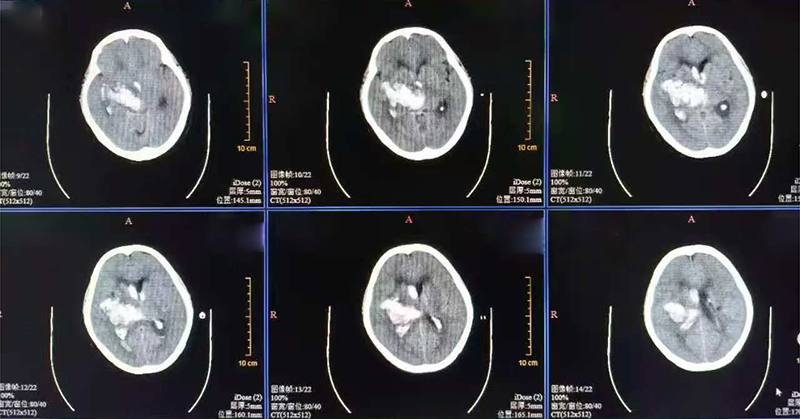

术前